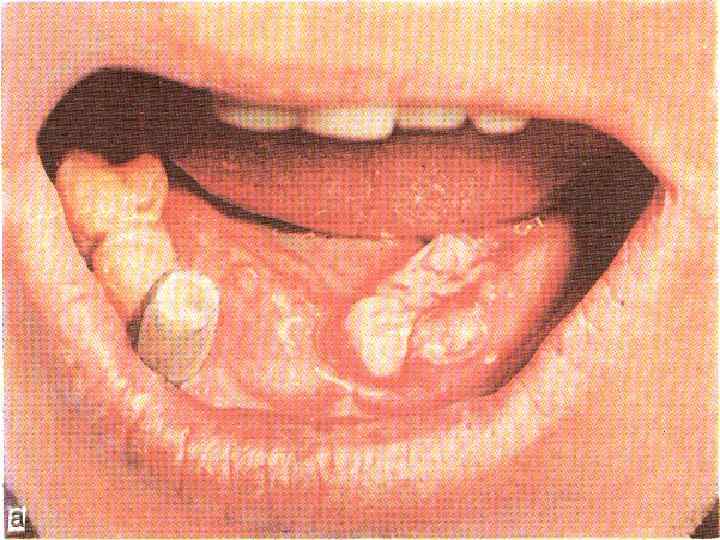

Рак слизистой оболочки щеки • Развивается на фоне лейкоплакии у курящих мужчин старше 50 лет; • Локализуется по линии смыкания зубов; • Рак переднего отдела протекает более благоприятно, чем заднего; • Морфологическая форма – плоскоклеточный рак; • Язвенно-инфильтративная или бородавчатая форма; • Метастазирует в нижнечелюстные и подбородочные лимфоузлы

Рак слизистой оболочки щеки • Развивается на фоне лейкоплакии у курящих мужчин старше 50 лет; • Локализуется по линии смыкания зубов; • Рак переднего отдела протекает более благоприятно, чем заднего; • Морфологическая форма – плоскоклеточный рак; • Язвенно-инфильтративная или бородавчатая форма; • Метастазирует в нижнечелюстные и подбородочные лимфоузлы

Рак слизистой оболочки щеки

Рак слизистой оболочки щеки